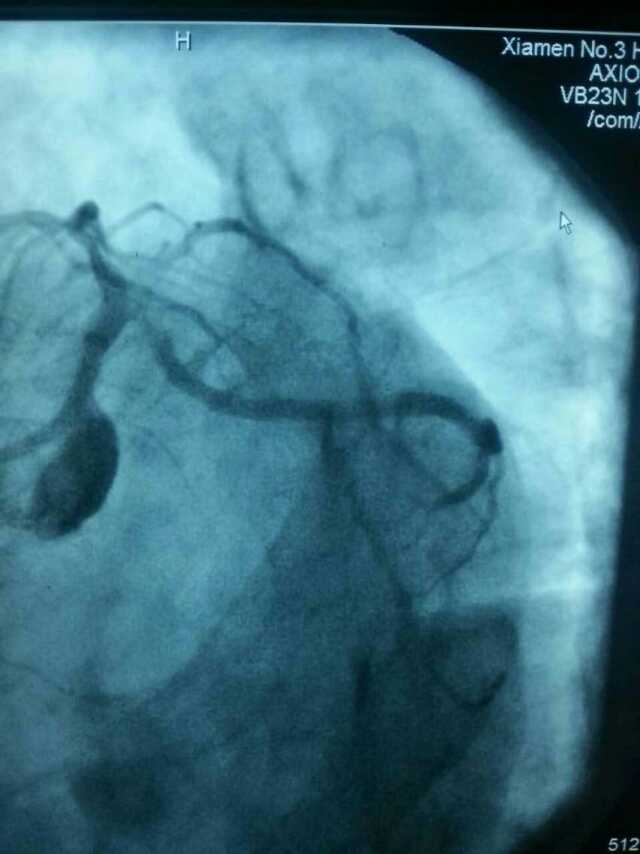

3月20日,家住翔安的庄先生为感谢跳蛋视频 心血管内科的医护人员在第一时间对他的病情给予明确诊断,并及时采取有效治疗措施,让他的心脏病很快得到康复回家。特地送来一面写着“德医双馨,妙手回春”锦旗以表达他们满满的感激之情。